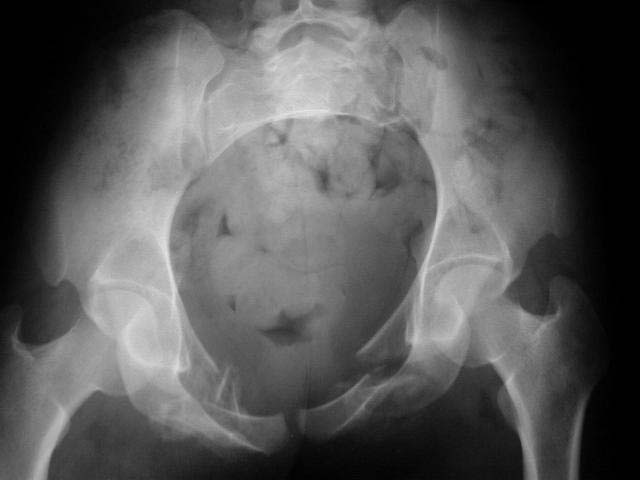

2 days ago I was asked by a local rehab hospital to evaluate a 21 yo female who while visiting out of town was thrown from a walk bridge (fall 20-30 ft). She sustained a left sided lateral compression pelvic ring injury and a fracture dislocation of the left elbow. The injury occurred on 9/1/01 and the treatment of her pelvic injury was skeletal traction and the elbow was splinted only (now subluxed with a comminuted radial head fracture and no motion). Her elbow is a priority a will be addressed.

An example of our current approach to similar injuries - A 26 y.o. male admitted to us Aug 23, 2001 6 weeks after injury (compression by a wheel of a truck).

An external fixator was applied and gradual reduction was started - lateral traction to mobilize sacral fracture and then the hemipelvis was moved downward. Then lateral compression was performed. Yesterday iliosacral screws was inserted.

Probably the best treatment is avoiding this situation. Educate the individuals involved in her initial evaluation. Teach them the importance of clinical and radiographic patient evaluations. Teach them exactly how to examine an injured pelvis. If it had been examined initially, the clinical instability would have been obvious. The radiographs reveal bilateral, comminuted, displaced anterior ramus fractures along with a sacral fracture which violates the anterior, middle, and posterior portions of the sacrum (analogous to a complete sacroiliac dissociation)....a "3 column injury"(if you pretend that the sacrum is a vertebra), so to speak.